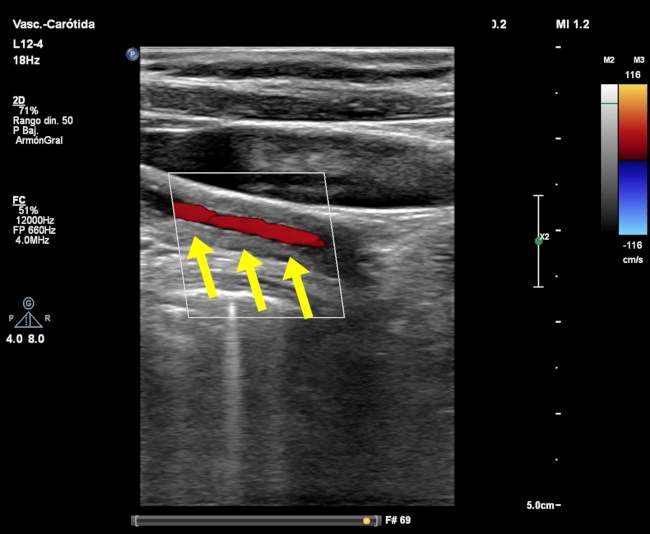

El signo del macarrón fue descrito por primera vez por Hiroaki Maeda en 1991. En su estudio de 23 pacientes con diagnóstico de arteritis de Takayasu (AT), demostró el engrosamiento difuso del complejo mio-intimal con ecografía modo-B en 19 pacientes.1 El engrosamiento parietal homogéneo de la carótida (►Fig. 1 y ►Fig. 2) se asemeja a un tipo de pasta, el macarrón, de característica forma tubular (►Fig. 3).

El análisis de la pared arterial mediante ecografía muestra la presencia de dos líneas ecogénicas paralelas, separadas por un espacio hipoecoico o anecoico. La línea ecogénica interna se corresponde la transición luz-íntima, siendo la línea más externa correspondiente a la interfase media-adventicia. El espacio comprendido entre ambas líneas ecogénicas se corresponde al engrosamiento combinado de la íntima y la media. El engrosamiento difuso y circunferencial de la arteria carótida permite observar el signo del macarrón, que es difícil de reconocer mediante angiografía.2

No hay pruebas de imágenes o de laboratorio diagnósticas consideradas gold standard para el diagnóstico de AT. La falta de sensibilidad o especificidad de los métodos, sumada a los síntomas constitucionales inespecíficos, hace que exista una demora en el diagnóstico de la enfermedad.4 Si bien la angiografía con sustracción digital ha sido tradicionalmente el método de elección para el diagnóstico de AT, la misma no permite evaluar los cambios patológicos de la pared arterial. Por otro lado, la ecografía es un método no invasivo y particularmente útil en la evaluación de la arteria carótida, reconociendo un engrosamiento circunferencial y homogéneo de la pared arterial.3